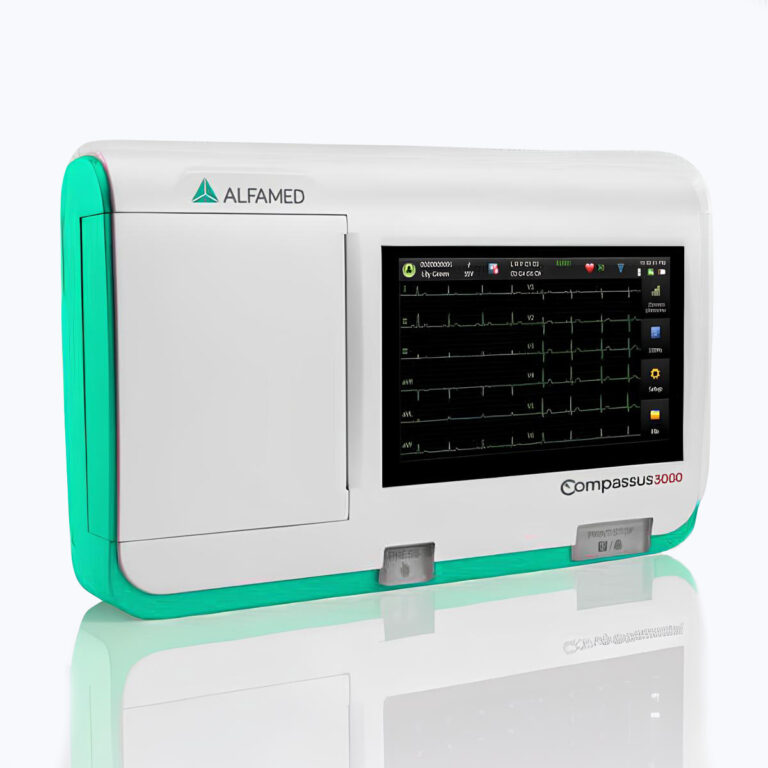

⦁ Monitor LCD touchscreen de 8.4’’;

⦁ Ajuste de rotação do painel;

⦁ Módulo de ECG (opcional)